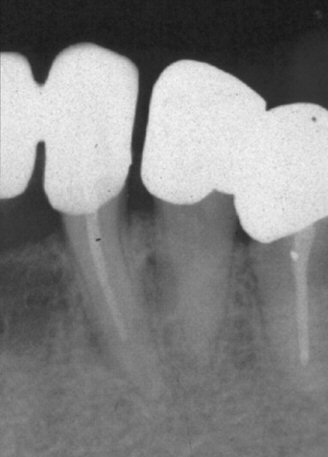

Πλάγια ριζική κύστη .

• Είναι οδοντογενής κύστη που εντοπίζεται κατά μήκος  της ρίζας ενός μη ζωντανού  δοντιού.

• Συνήθως αναπτύσεται στην έξοδο ενός παράπλευρου ριζικού σωλήνα ενός δοντιού με νεκρό πολφό.

• Ακτινογραφικά εμφανίζεται ως μια μικρή μονόχωρη ακτινοδιαύγαση με σαφή και συνήθως υπεροστικά όρια.

Περιστατικό πλάγιας ριζικής κύστης